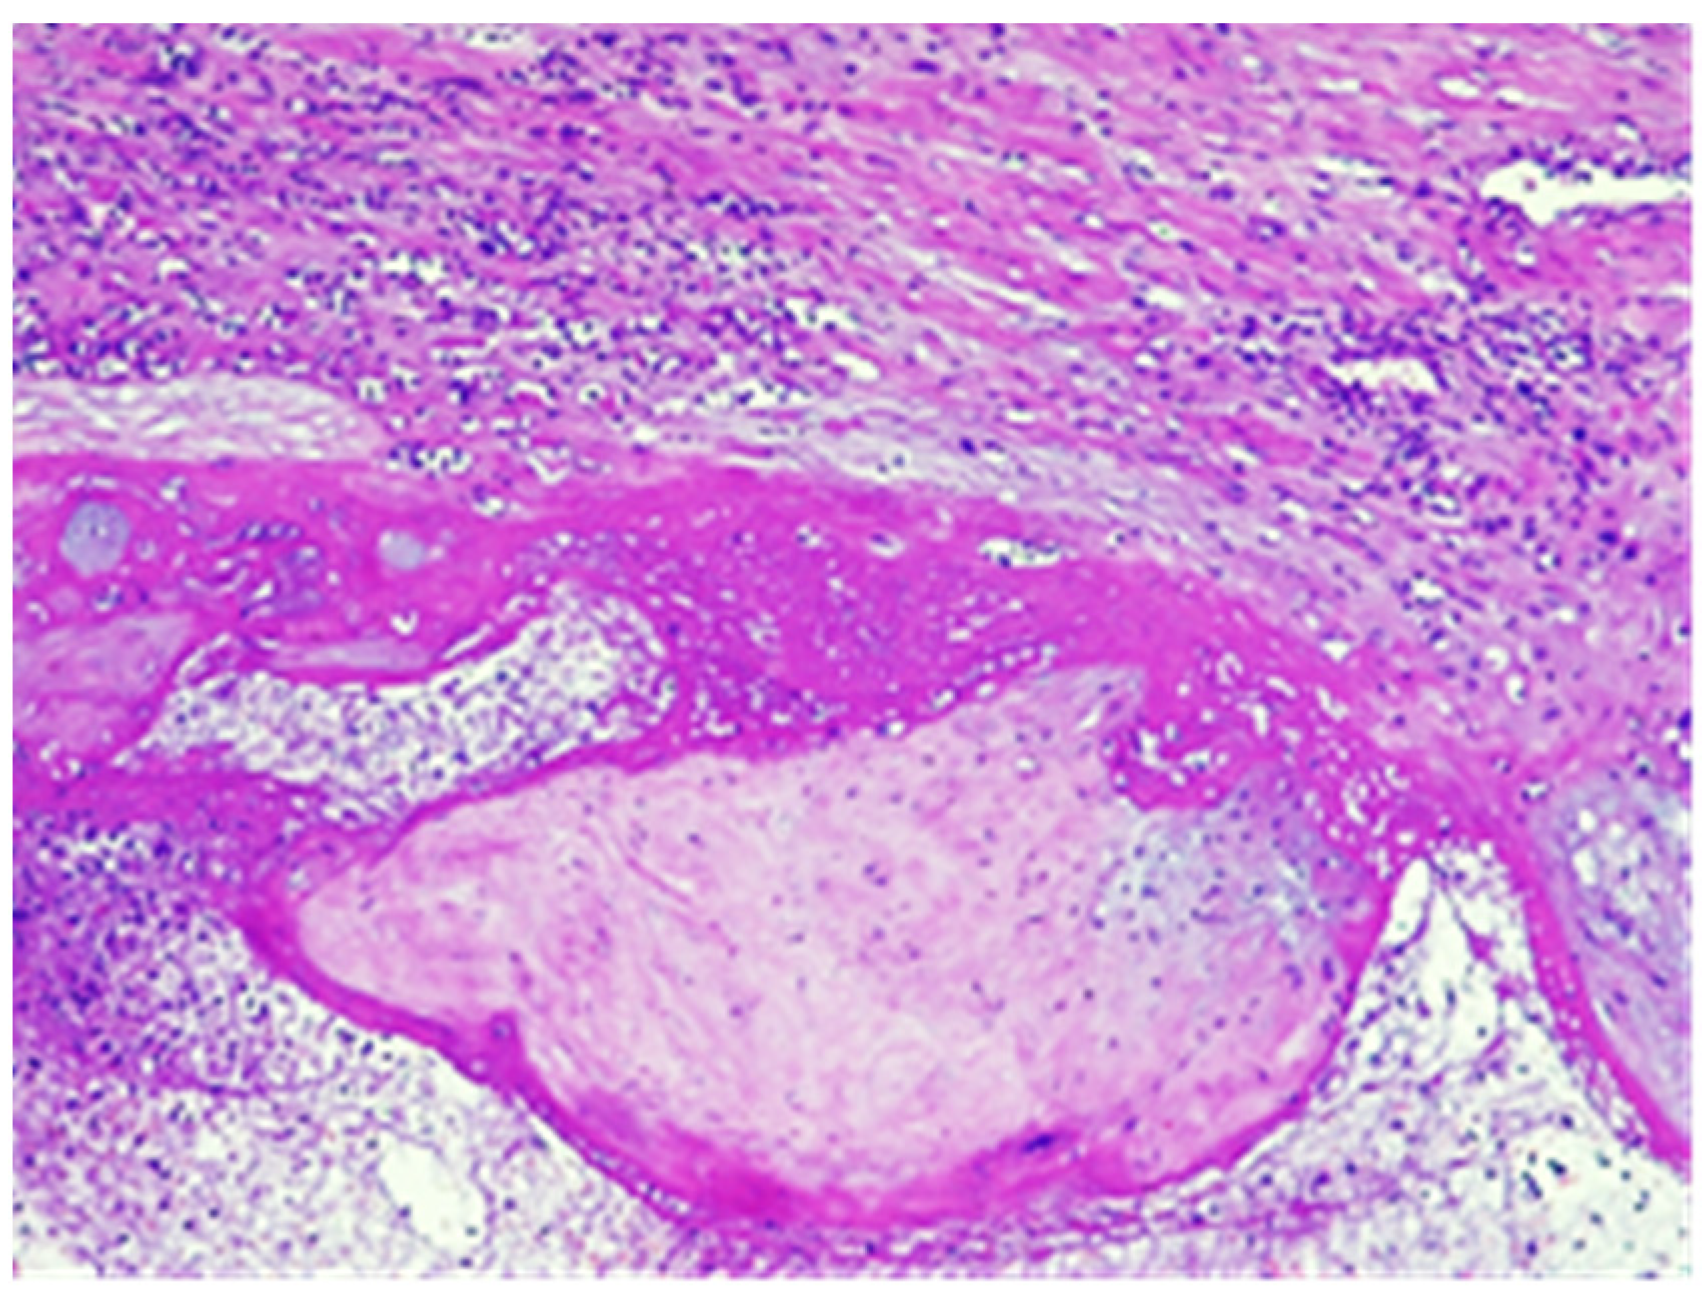

Figure 10.

Necrotic chorial villi (A) included in fibrino-leucocytic exudate (B) in the vicinity of the large vessels in the external half of the wall, hematoxylin and eosin stain, × 4.